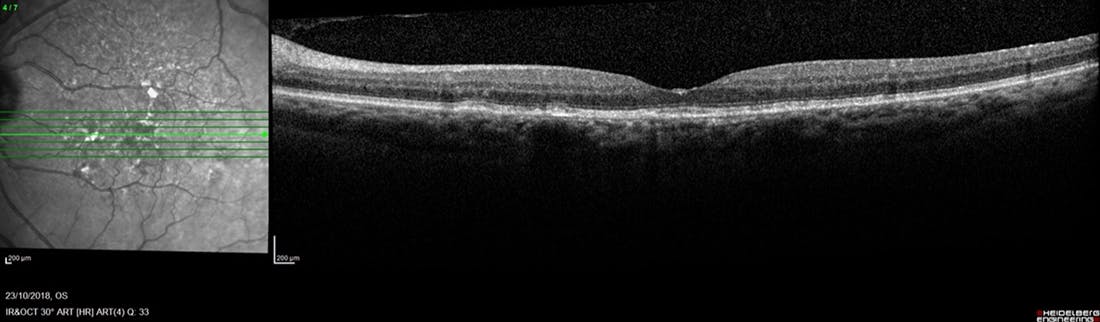

A 73-year-old woman was evaluated in our clinic in October 2018. At the time of the visit, the right eye was being treated for wet age-related macular degeneration (AMD) with quarterly intravitreal anti-VEGF injections. The left eye showed pigmentary changes, drusen, and normal foveal contour with no signs of atrophy (Figures 1 and 2).

<p>Figure 1. Near-infrared reflectance image of a left eye of a 73-year-old woman captured in October 2018 showing pigmentary changes and drusen.</p>

Figure 1. Near-infrared reflectance image of a left eye of a 73-year-old woman captured in October 2018 showing pigmentary changes and drusen.

<p>Figure 2. OCT of the same eye as shown in Figure 1 showing normal foveal contour and no signs of atrophy.</p>

Figure 2. OCT of the same eye as shown in Figure 1 showing normal foveal contour and no signs of atrophy.